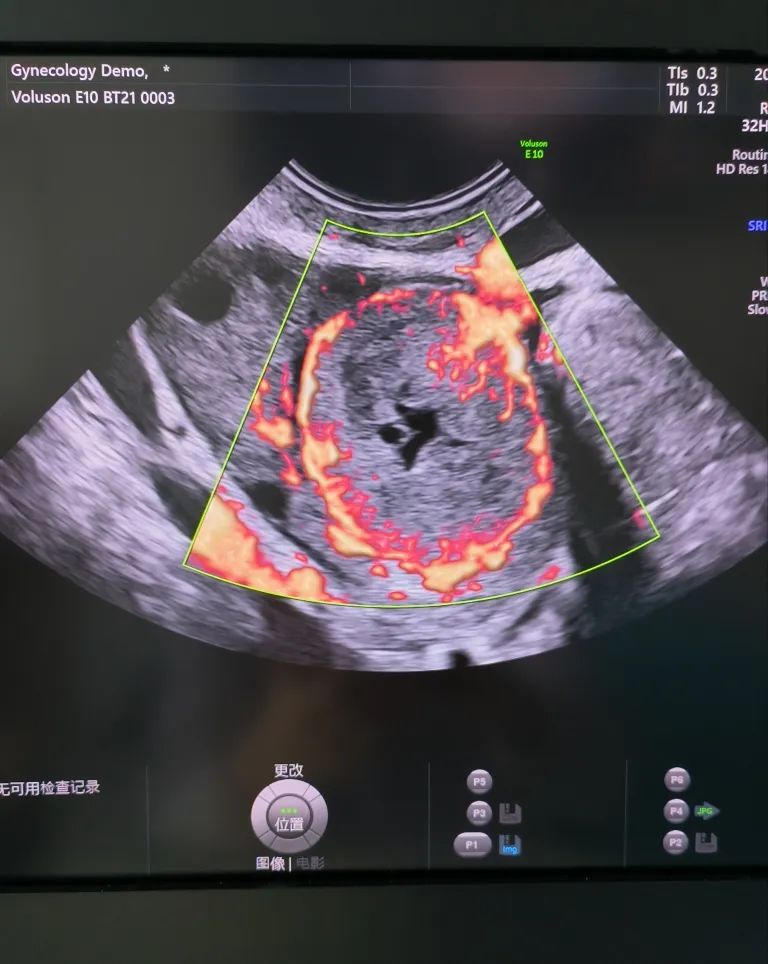

經陰道超聲是在陰道超聲探頭上套上避孕套,將探頭伸入陰道進行檢查。由于探頭位置接近子宮和卵巢,圖像更清晰,檢查結果更準確。而且不需要憋尿,相對節(jié)省時間。所以現(xiàn)在大部分醫(yī)院對有性生活史的婦女更愿意開展經陰道超聲檢查。